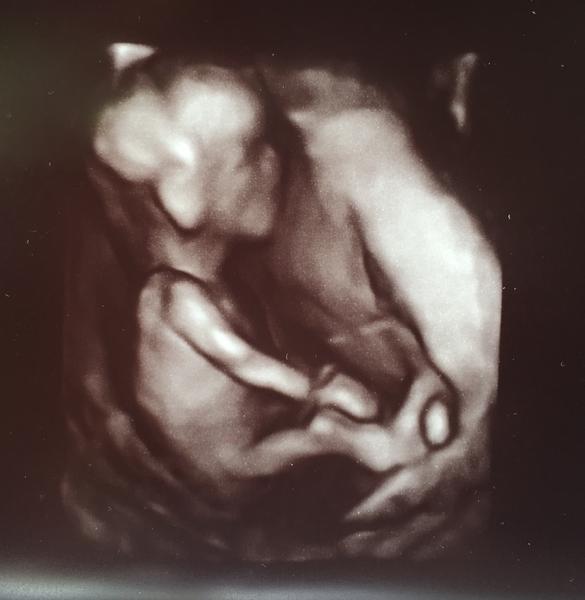

Môj mini prcek 😄😄

@xenabojovnica kraaasna fotecka 😍 my ideme o tyzden a uz sa tesiiiim, pevne verim a dufam ze bude vsetko v poriadku 😊